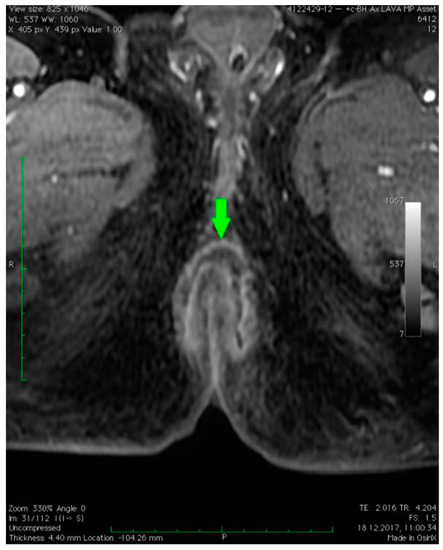

3. Case Presentation